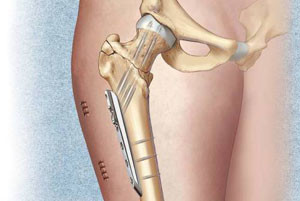

Титановые пластины при травмах нижних конечностей. Переломы в области бедра, коленного сустава и в других частях ноги требуют при лечении установки титановой инертной пластины. Используется она с целью крепления перелома таза, а также при травме лонной кости и при разрыве лонного симфиза. Необходимость в ее применении возникает в случае перелома подвздошной и седалищной костей. Пластины можно накладывать в области ноги, когда кости неправильно срослись или же долго не срастаются. Но прежде, чем соединять кости, необходимо удалить осколки или часть кости и мягких тканей, которые повреждены.

Если в наличии сложный перелом бедра, то используют аппарат Елизарова. Его также задействуют в случае долго не срастающихся переломов.

Специальный штифт вводится в канал кости при переломе тела бедра. Он фиксируется с помощью винтов. Для точного введения и фиксации травматолог использует прибор под названием навигатор.